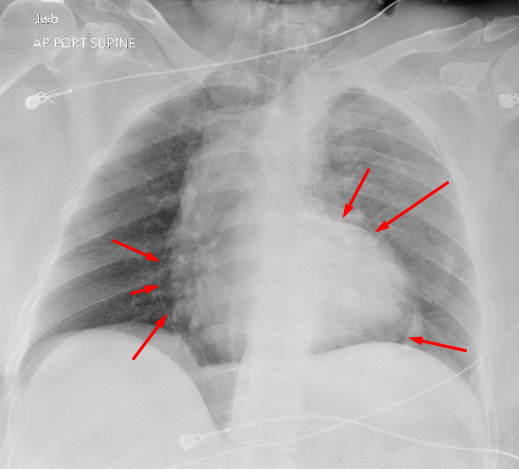

Sample ReportPneumopericardium.

Multiple left posterior rib fractures with a small left pneumothorax. No mediastinal shift.

Query lucency outlining the right hemidiaphragm, which could represent pneumothorax layering anteriorly on this supine radiograph. Consider CT for further assessment.

Asymmetric hazy opacification of the left hemithorax, which may represent a layering pleural effusion. No focal airspace opacification.